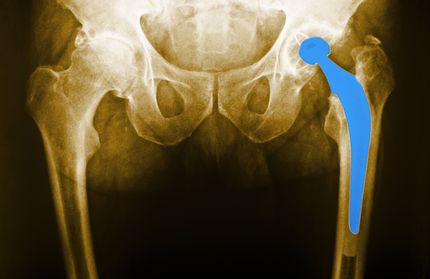

HIP PROSTHESIS,  X-RAYThe end of January marked the last time certain plaintiffs in DePuy metal-on-metal hip implant lawsuits could either continue their lawsuits or voluntarily dismiss them. These metal hip implant lawsuits were part of a DePuy metal-on-metal hip MDL (multidistrict litigation) against Johnson & Johnson and DePuy Orthopaedics.

Plaintiffs allegedly experienced severe DePuy ASR metal hip implant side effects. These hip replacement side effects were allegedly caused by the metal rubbing against metal and releasing small metal particles into the bloodstream, which can cause a myriad of side effects including metal poisoning, cancer, or a failure of the DePuy metal hip implant. Many plaintiffs in DePuy metal hip implant lawsuits had to undergo revision surgery in order to remove the faulty metal-on-metal hip.

DePuy ASR metal hip implant side effects include early failure of the hip, dislocation, toxic and/or metallic substances leaked into the bloodstream, cancer, loss of bone strength, tissue death, and more.

DePuy had received so many reports of DePuy metal hip implant failure and side effects that they recalled the product in 2010. Many failures occurred within five years of use. DePuy hip lawsuits began to be filed shortly after that. Plaintiffs accused Johnson & Johnson and DePuy of failing to warn against potential side effects.